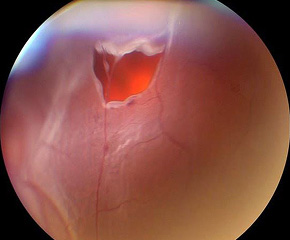

망막박리 수술 전

망막박리 수술 후